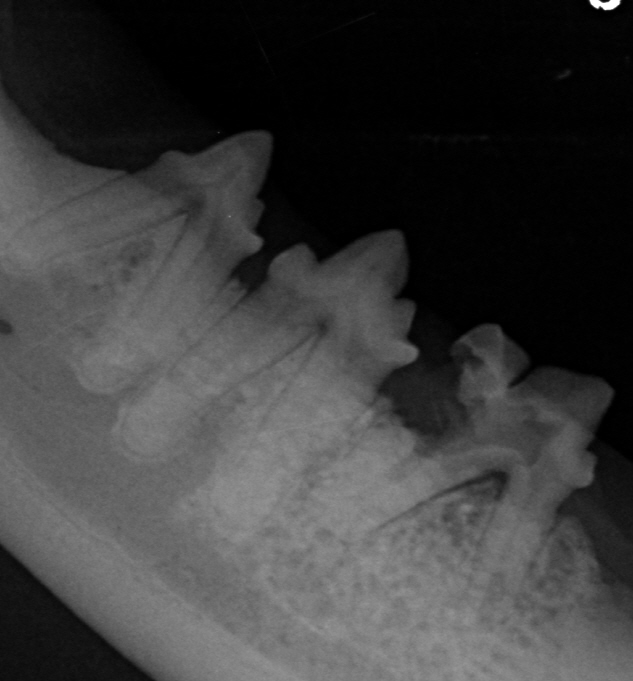

Bedeutung des Dentalröntgens:

Dentalröntgen ist unerlässlich, um resorptive Läsionen sicher zu diagnostizieren. Viele Läsionen sind nur unter dem Zahnfleisch sichtbar und können bei der reinen Mauluntersuchung nicht diagnostiziert werden. Röntgen ermöglicht:

- Erkennung von frühen unter dem Zahnfleischrand befindlicher Veränderungen

- Unterscheidung der Läsionstypen und somit Planung der geeigneten Therapie (Extraktion oder Kronenamputation)